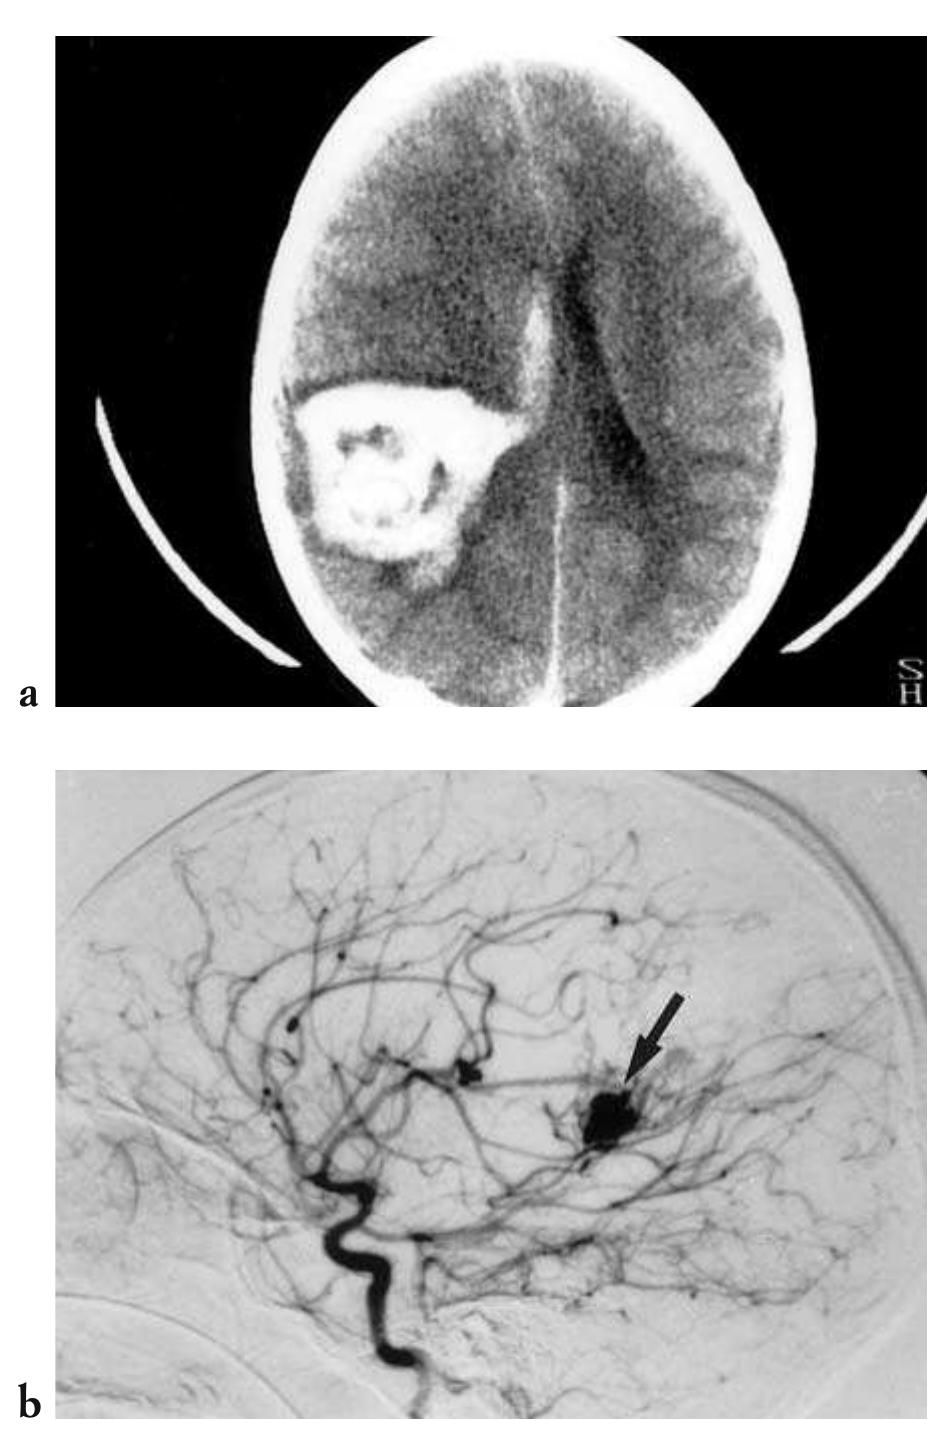

![Fig. 4.15 - Epidural haematoma. The CT examination shows a biconvex blood collection over the right temporoparietal region asso- ciated with marked mass effect. Note the displacement of the surrounding parenchymal structures associated with leftward midline subfalcian herniation and compression of the right lateral ventricle. In the more caudal scan, ipsilateral downward herniation of the uncus is also clearly visible. In addition, there is a fracture in the right temporal bone, with minor fragment displacement. CT follow up three months later documents encephalomalacia of the posterior temporal lobe, perhaps as a result of infarction secondary com- pression-occlusion of the posterior cerebral artery caused by the uncal herniation. [a,,) initial axial unenhanced CT with brain win- dows; b,,) initial axial CT with bone windows; c) three month follow up axial CT].](https://figures.academia-assets.com/35610716/figure_271.jpg)